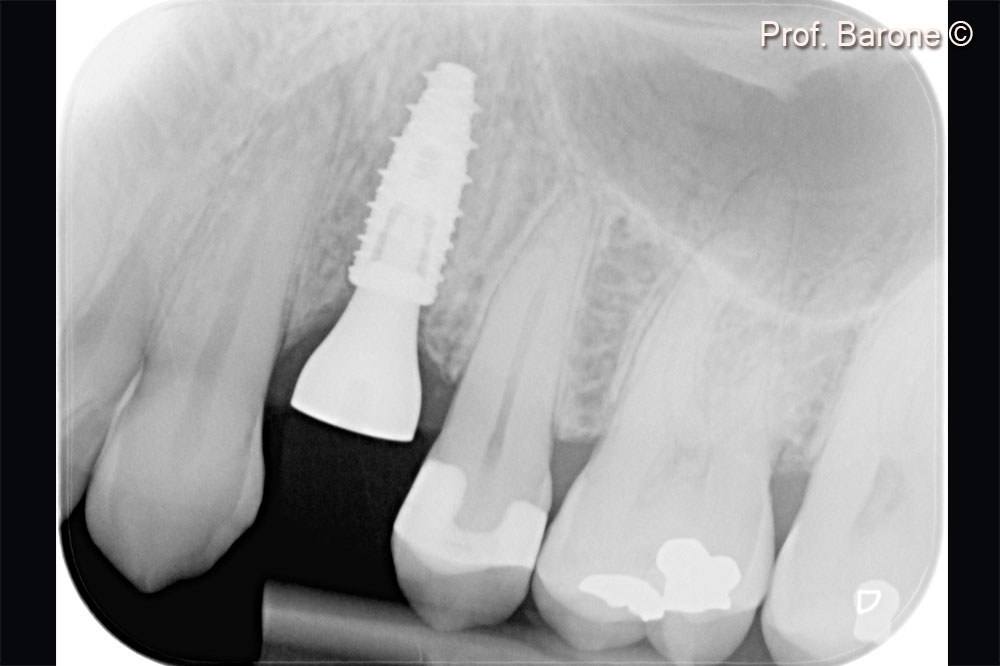

Periapical radiograph after implant placement